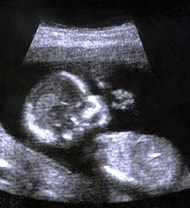

妊娠5ヶ月(18週目)

赤ちゃんが指しゃぶりを開始

赤ちゃんの発育は、頭、特に口から始まります。この時期から指しゃぶりを始めるようになり

ます(上記の写真を参考)。一緒に羊水を飲み込むこともありますが、これは呼吸の練習や生まれてからおっぱいを吸うための訓練になっています。